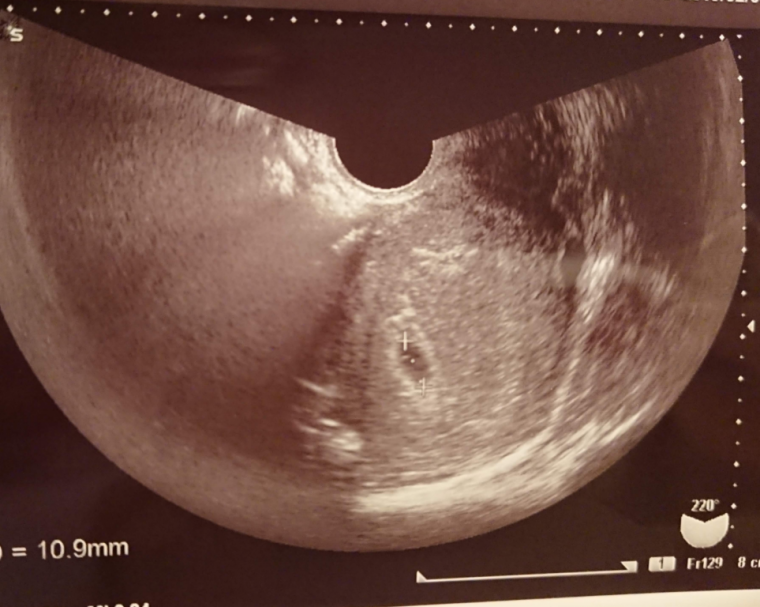

5周4日 胎嚢

妊娠5週4日 5w4d の超音波 エコー 写真

妊娠5週4日 5w4d の超音波 エコー 写真

第3話 5週4日 卵黄嚢が確認できました 胎嚢の大きくなり方物語 妊娠ぱっぴー

妊娠5週 3 6日 のエコー写真 体験談

5週4日でのエコー写真について教えて下さい 妊娠のq A 解決済み Okwave

5週4日目 前回と比較 2019 10 14 初産 現在41歳 2人目妊活中

5週4日 みんな違ってみんないい

妊娠5週 5w4d で6 3ミリの胎嚢確認 平均よりも胎嚢サイズ小さい むきだしのことば ワーママえむのブログ

Happy Life 妊娠5週4日目 出血が

妊娠5週4日目 左側の腹痛と微量出血で受診したら胎嚢確認できた 保育士うたブログ

胎嚢見えました 妊娠2ヶ月 5週4日 の写真 ベビカム成長記録 妊娠 出産 育児に関する総合情報サイト ベビカム

5週4日目なう Blaue Erde

妊娠5週5日に胎嚢と心音 心拍 を確認 胎嚢と胎芽のエコー写真 画像あり 大きさや形

妊娠5週5日に胎嚢と心音 心拍 を確認 胎嚢と胎芽のエコー写真 画像あり 大きさや形

質問 Itmedia 5週4日でのエコー写真について教えて下さい

エコー写真に詳しい方宜しくお願いします 本日前回生理から計算して5週4 Yahoo 知恵袋